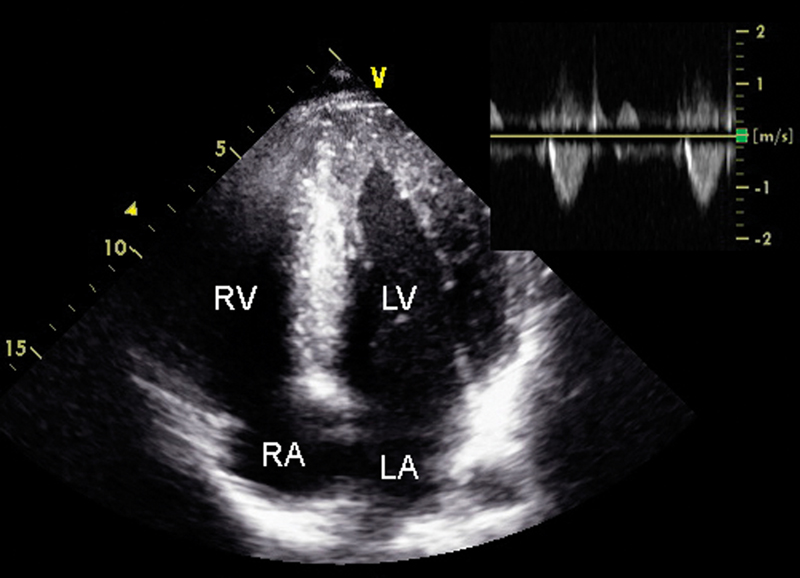

فحوصات تشخيصية لبعض امراض القلب والشرايين التاجية